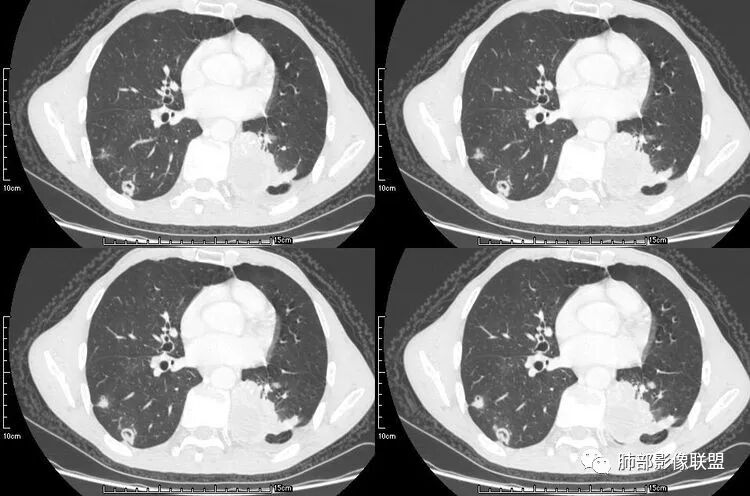

患者老年男性,咳嗽、咳痰、痰中带血伴胸闷2月余。长期大量吸烟史。查肝肾功能、血糖、血脂、心肌酶、电解质、血沉、C反应蛋白、抗“O”、类风湿因子、抗核抗体谱无明显异常。肿瘤标志物提示NSE、CYFRA21-1稍升高。胸部CT:肺气肿背景,左肺下叶后基底段不规则肿块影,见支气管截断,内见大片状低密度区及部分血管影,增强轻度强化,远端空洞形成。双肺多发不规则实性结节影、见毛刺、胸膜牵拉及血管集束,结节内见空洞形成,部分可见血管影,多位于胸膜下。双肺见多发肺大泡。综合考虑左下肺恶性病变并双肺转移。鳞癌或淋巴瘤可能。鉴别血管炎性病变及真菌感染。

本病例左肺下叶肿块,有深分叶、毛刺、胸膜牵拉凹陷、支气管截断及纵隔内淋巴结肿大等征象,都均支持病灶为恶性,如腺癌,而且叶间裂的多发结节也提示是腺癌来源可能大;双肺多发结节、肿块,大部分病灶有分叶、毛刺及胸膜凹陷的恶性征象,与原发肿瘤本身的性质有关,所以应该与左肺下叶肿块同源,而且双肺多发病灶内空洞也具有多样性;

此病例中空洞形态多样,内壁不光整,有分隔影,周围未见明显卫星灶及钙化灶,结核不太符合;患者病史慢性病史,无明显发热,缺乏中毒临床表现,急性感染基本排除;各种中性粒细胞胞浆抗体阴性,没有鼻窦炎,肾脏等病史,基本排除血管炎;霉菌性空洞常见于免疫机能低下者, 常为空洞、肺炎、伴“ 晕圈”征的结节及支气管扩张合并存在。